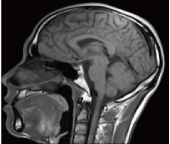

“脳ドック”は、脳卒中(脳梗塞・脳出血・くも膜下出血)・認知症の早期発見や、脳動脈瘤、脳腫瘍のスクリーニングを行います。「脳」に関係する詳細な検査を行い、『 ”脳”の病気を予防 』しましょう。

当院は、1.5テスラのMRIシステムを使用。

脳ドックは、「脳」に焦点を絞って、その状態を詳しく調べる専門ドックです。 脳動脈瘤、脳腫瘍、脳梗塞、脳出血の症状が現れる前にそれらの危険因子を発見することを主な目的としています。自覚症状のないうちに今の脳の状態をチェックしましょう。